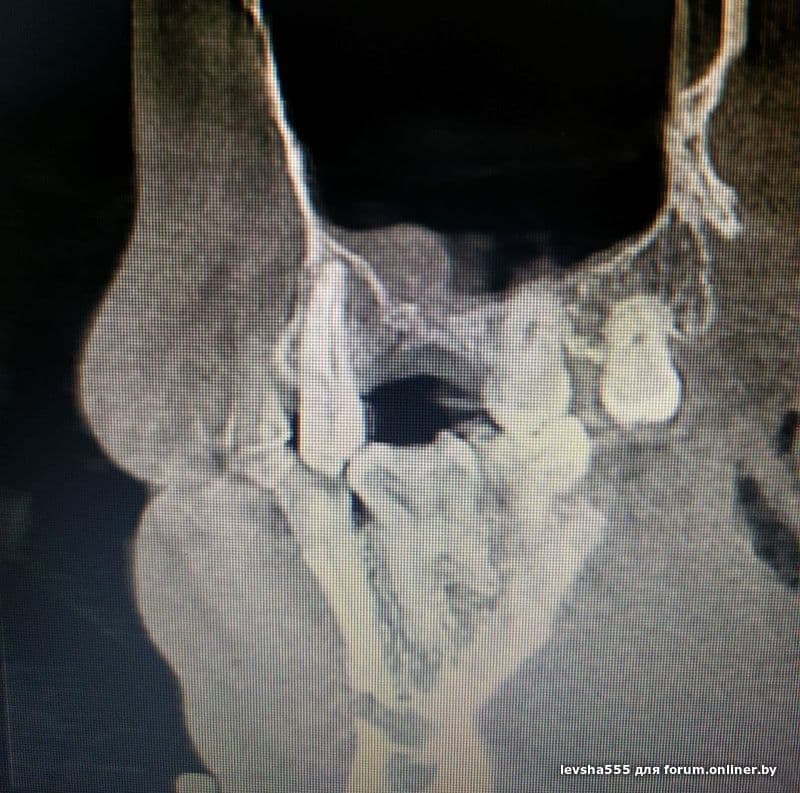

Добрый день форумчане стоматологи. Может кто-нибудь подскажет по данной проблеме. Этим летом в июле удалил 6 зуб справа сверху (вылез свищ перед этим). Далее через неделю после удаления свищ закрылся. И вот в ноябре, на месте удаленного 6 зуба в десне на внешней части снова вылез свищ. Сделал КЛКТ но к хирургу с этим диском еще не попал. Подскажите в чем может быть проблема , почему свищ снова появился ? прилагаю скриншоты c КТ за месяц до удаления зуба и с КТ сделанного вчера.

levsha555:Добрый день форумчане стоматологи. Может кто-нибудь подскажет по данной проблеме. Этим летом в июле удалил 6 зуб справа сверху (вылез свищ перед этим). Далее через неделю после удаления свищ закрылся. И вот в ноябре, на месте удаленного 6 зуба в десне на внешней части снова вылез свищ. Сделал КЛКТ но к хирургу с этим диском еще не попал. Подскажите в чем может быть проблема , почему свищ снова появился ? прилагаю скриншоты c КТ за месяц до удаления зуба и с КТ сделанного вчера.